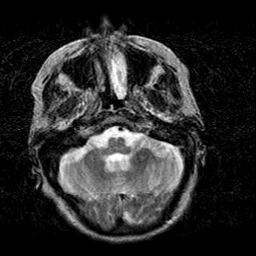

Creutzfeld-Jakob disease: T2-weighted MR -- Slice #4

[Home][Help][Clinical] Slice 4